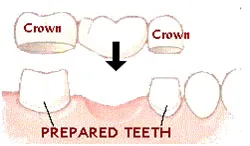

FIXED OPTIONS:

Crown and bridge work

The teeth adjacent to the gap are cut down. A false “cap” resembling a tooth is cemented onto the teeth that are cut down. These caps hold a false tooth which replaces the missing tooth

Advantages

- Good aesthetic result

- If looked after well can last for life

- Cannot be removed from ones mouth

Disadvantages

- Must cut down the tooth/teeth adjacent to the gap/s to support the false tooth

- More tricky to clean than other options

TAKING CARE OF YOUR CROWNS AND BRIDGES

Crowns, bridges and veneers are expensive privileges placed in the mouths of individuals who are considered most able to take care of them.

One cannot place this type of work in the mouths of patients whose oral hygiene is not of a certain standard. That you have had this work done in your mouth means that you meet the above criteria.

It is now essential that you follow the maintenance programme to ensure that all effort is made to reduce any possible risk of failure of your crowns.

The maintenance programme consists of 3 components :

- Brushing your teeth – especially at night. Do this gently as you do not want to expose the crown margins.

- Floss daily – unfortunately this is the only way to clean between the teeth. You need to ensure that the junction where the crown and the tooth meet is kept clean.

- Rinsing with a mouthrinse – preferably a fluoride mouthrinse. Once a day only.

- Any sensitivity must be discussed with me immediately. Be responsible and ensure that you see the hygienist every 6 months.